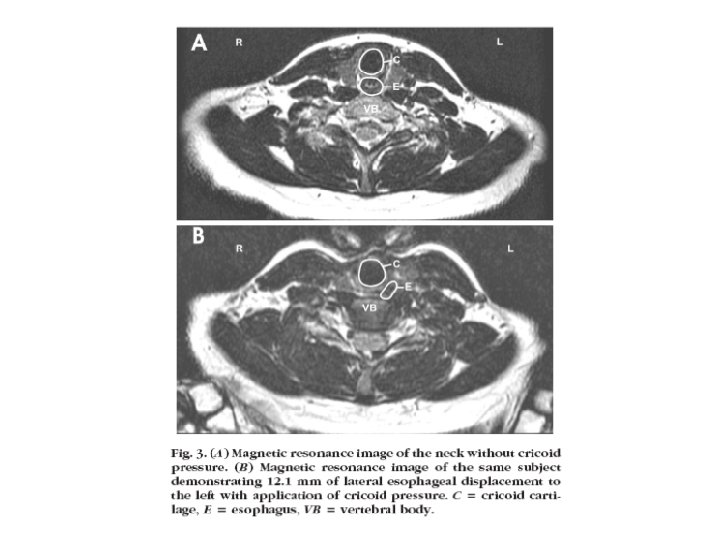

Induction anesthésique • Séquence rapide • Thiopental : hypnotique de référence 5 mg/kg • Kétamine, étomidate, propofol • Succinylcholine 1 – 1, 5 mg/kg • Pression cricoïdienne (Sellick) 20 N avant la perte de connaissance et 40 N après (seringue de 50 cc)